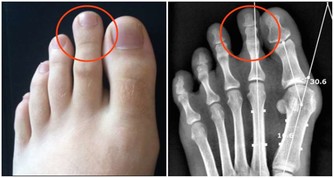

為了時尚、個性,有的女人一年四季都穿裙裝,膝蓋和關節暴露在外,難免遭受風、寒、濕等外邪的侵擾,引起關節疼痛。

很多這樣的女性,她們歲數都不大,但早早就有了腿痛的毛病。

關節部位受寒疼痛,可不是一天兩天形成的,正所謂,冰凍三尺非一日之寒。